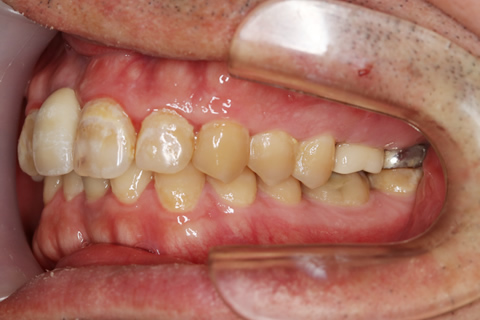

治療前

インプラント埋入時

治療後

- 年齢・性別

- 35歳男性

- 治療期間

- 3ヶ月

- 抜歯

- 右上1.3左上6.7の残根抜歯

- 治療費

- 123.2万円

- 備考

- 右上1.3左上6.7の欠損部

- 治療内容

- 4本のインプラントを一回のオペで埋入。

- 施術の副作用(リスク)

- オペによる知覚障害。インプラントによる歯肉炎。インプラント脱落。